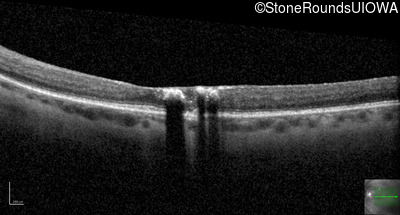

Age at visit: 47 years

OD OS

This 47 year old woman began wearing glasses at age 5 and had cataract surgery at age 32. At that time her doctor noticed a retinal abnormality.